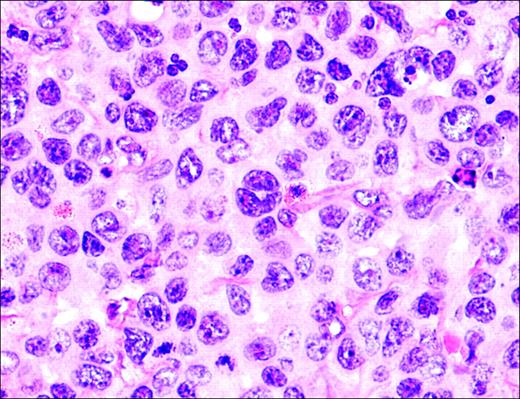

Anaplastic large-cell lymphoma. Infiltrate is composed of large transformed lymphocytes, including hallmark cells with kidney-shaped nuclei.

Pathology

The morphology of ALCL, systemic type, consists of large lymphoid cells with pleomorphic or multiple prominent nuclei and abundant cytoplasm (Figure 3). Tumor cells grow in a cohesive pattern, and there is often sinusoidal spread in the lymph nodes. Tumor cells express CD30 and either T cell or no specific lineage antigens (null cell).